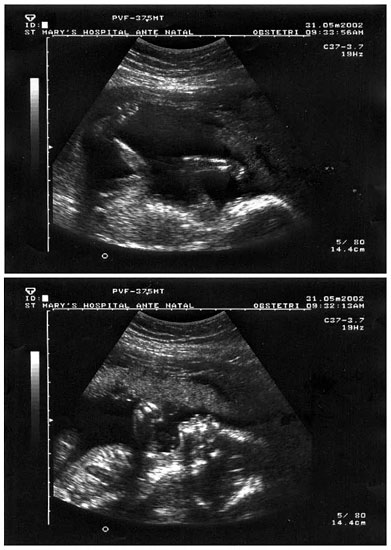

Mary & Jason's 21 week scan

31 May, 2002